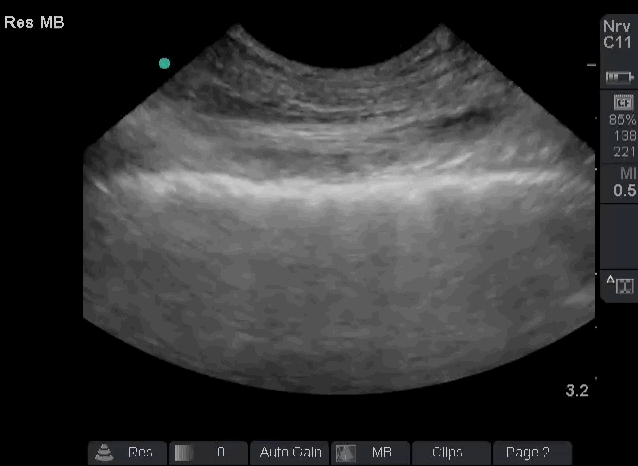

Chest radiograph is ordered and is pending. In the interim, bedside lung sonography is performed, and the following finding is present bilaterally at multiple points of examination.

Based on the ultrasound findings, which one of the following can be ruled out as a cause of dyspnea:

A. Pneumothorax

B. Pneumonia

C. Pulmonary embolism

D. COPD exacerbation